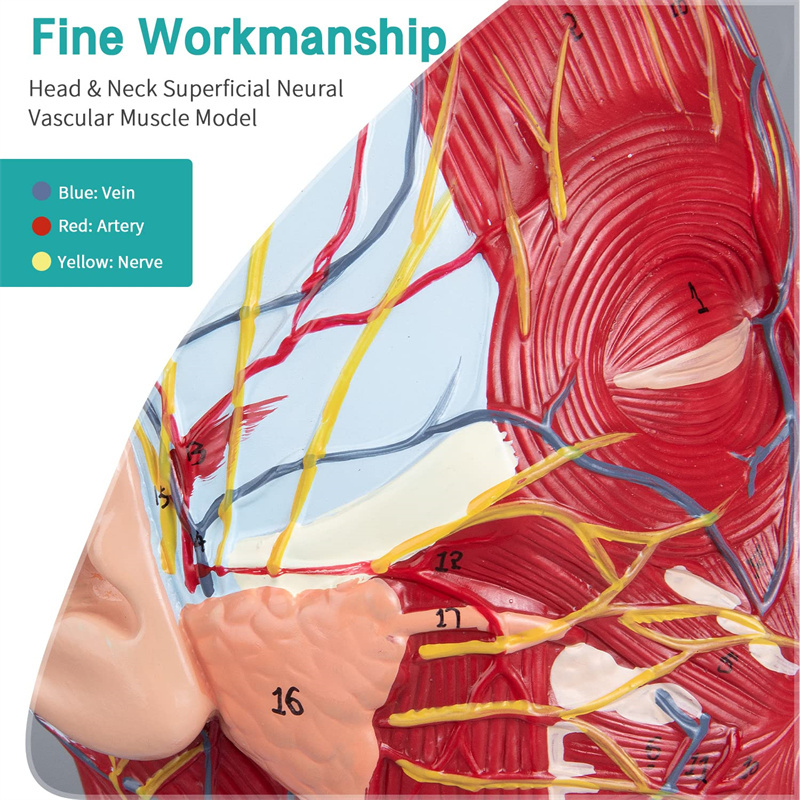

【Modelo superficial do músculo neurovascular】 Números altamente detalhados, marcados e destacáveis, aprofundar o entendimento dos músculos superficiais, vasos, nervos e as estruturas internas da cabeça e pescoço. Artéria vermelha, azul-veia, nervo amarelo.

【Apresenta】 mostra os músculos superficiais da face exposta; os vasos sanguíneos superficiais e os nervos do rosto e do couro cabeludo; as estruturas internas da glândula parótida e do trato respiratório superior; A estrutura de seção transversal sagital da coluna cervical.

Este modelo mostra detalhes do pescoço da cabeça direita e da seção sagital média do humano. incluindo o superficial

músculos da face exposta; os vasos sanguíneos superficiais e os nervos do rosto e do couro cabeludo; as estruturas internas

da glândula parótida e trato respiratório superior; A estrutura de seção transversal sagital da coluna cervical.

Este modelo é um modelo muscular neurovascular superficial grande e pescoço natural, um componente 1, mostrando os detalhes da cabeça e pescoço direito humano e seção sagital mediana, incluindo os músculos superficiais expostos da face, vasos superficiais do rosto e do couro cabeludo, nervos e a estrutura medial da glândula parótida e do trato respiratório superior, e a estrutura da seção sagital da coluna cervical